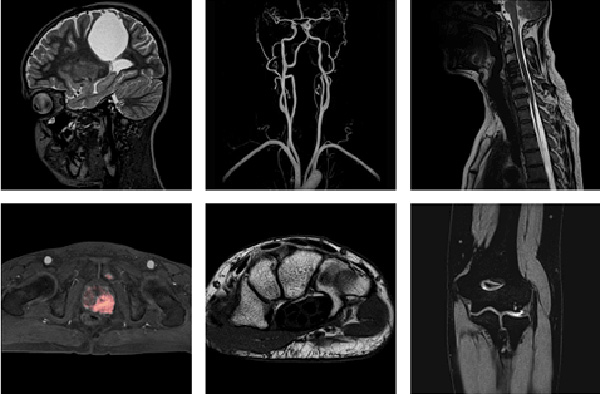

MRI는 강력한 자장내에 흐르는 RADIO파와 원자핵의 자성, 경사자장, 등의 상호 작용에 일어나는 신호를 이용한다. 환자 자세의 움직임 없이 여러 가지 방향의 사진을 얻을 수 있고 또한 연부조직의 대조도가 우수하고, x-ray의 피폭 염려가 없으며 특히 충추신경계통의 질환 진단에 탁월한 효과가 있다.

모든 부위 검사 가능

자기공명영상검사는 자기장을 발생시키는 기계가 고주파를 발생시켜 인체에 보내면, 인체 내의 수소원자핵의 반응으로 발생되는 신호를 컴퓨터로 계산하여, 인체의 모든 부분을 영상화하는 검사 방법입니다. 자기공명영상은 고주파를 이용하는 검사이므로 인체에 사실상 해가 없는 비침습적 검사로 조영제를 사용하지 않아도 전산화단층촬영검사보다 조직 간의 대조도가 우수합니다. 특히 신경, 근육 등 연부조직에 대한 대조도가 높아 진단적 가치가 우수한 검사입니다. 오산한국병원이 도입한 독일 지멘스社 1.5T MRI는 기존의 MRI 보다 빠른 검사시간, 고해상도 이미지, 전신촬영, 기능적 검사 등의 기능을 자랑한다. 특히 이 MRI는 뇌기능 분석을 상세하게 해 준다.